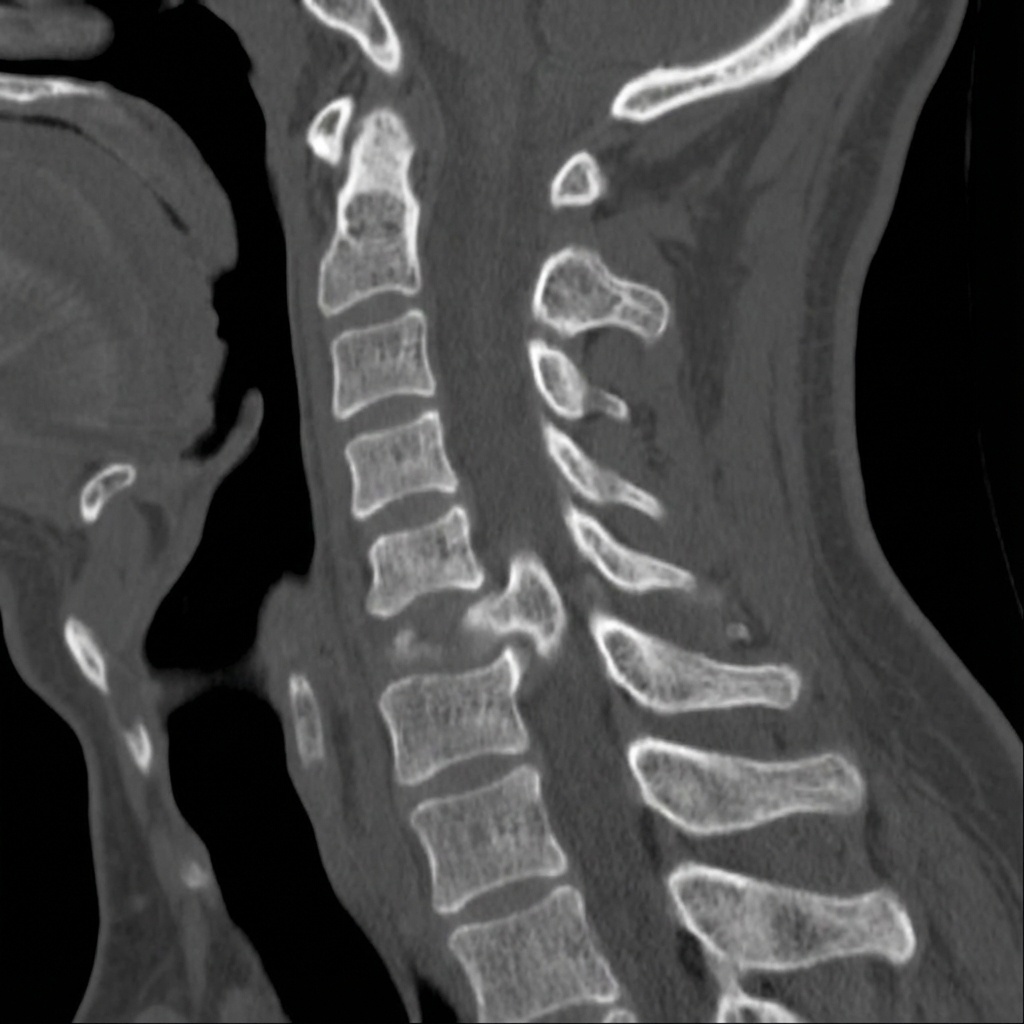

Sagittal and axial CT images demonstrating unilateral left facet dislocation at C6-7. The left C6 inferior articular process is locked anterior to the C7 superior articular process (jumped facet). There is approximately 25% anterior translation of C6 on C7 with rotation. The right facet is subluxed but not locked. This represents unilateral facet dislocation with associated radiculopathy pattern.

Describe the CT findings and classify this injury.